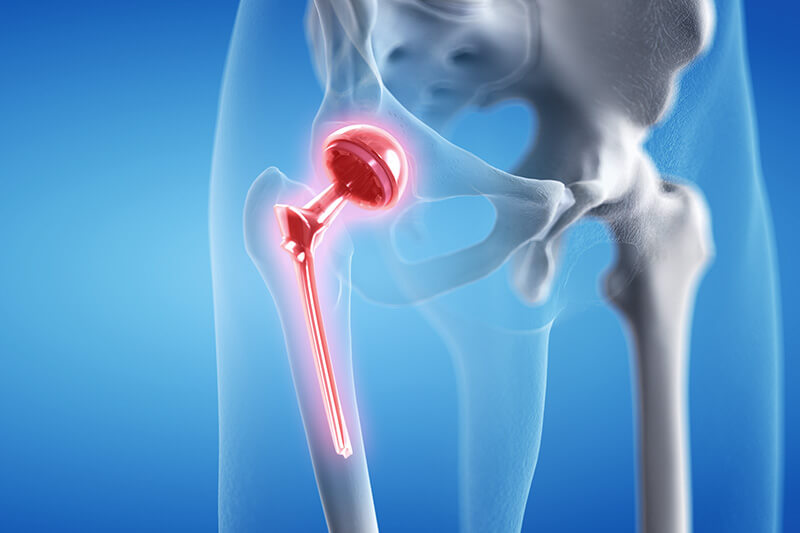

Knee replacement restores function and relieves pain with an artificial implant.

About 90% of first-time knee replacements last at least 15 years and many last at least 20 years. Patients can extend the life of their knee replacements by complying with their physical therapy routines and avoiding high-impact activities, such as jumping or jogging. High impact activities cause friction between the man-made components of the replacement knee, causing wear and tear.

General indications that you are ready for a total knee replacement:

-Bone on bone arthritis

-Persistent pain, with movement and at rest.

-Pain is disrupting your sleep.

-Pain is preventing you doing you activities of normal life.

Typically you are standing same day as surgery. You can start walking

next day after surgery. Most people discharge from hospital after 3 or 4

nights. People with difficult home situations or poorer mobility may

require a stay in rehab ward till they are proven to be independent.

Crutches or awalking aid is used for 2-4 weeks. People may return to

work as soon as 3 weeks, though some may need 3 months.

Having a joint replaced is a major operation. While most people have a good result and an active recovery, there are surgical and medical risks you need to be aware of. Ask your surgeon for more details.

You should follow the exercises provided by the hospital physiotherapist however you do not need to visit a physiotherapist once discharged. A hydrotherapy program may be suggested after your 2 week review.